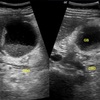

A

GB sludge

How well did you know this?